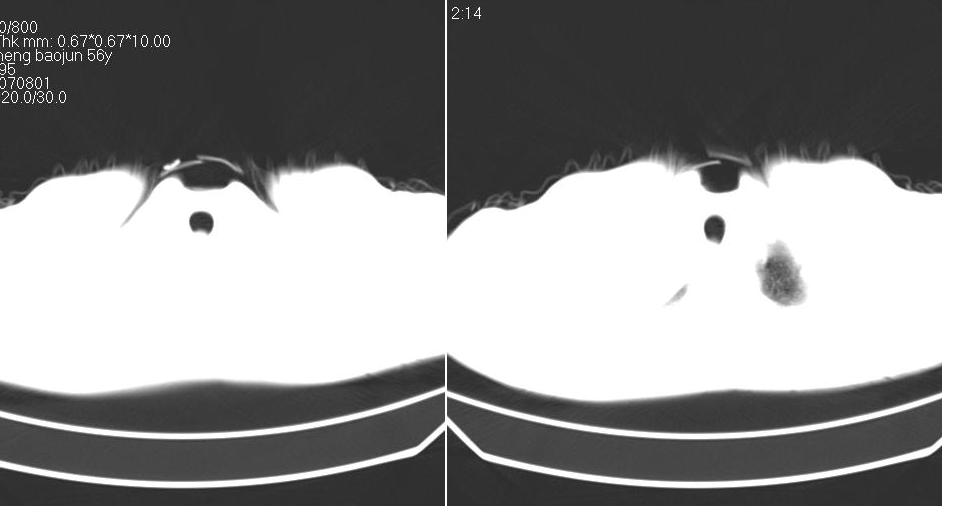

男 58岁 咳嗽,无明显不适.

右侧肺门肿块,右上叶不张,右上胸廓塌陷,气管纵隔右移,纵隔内有些小淋巴结,考虑中央型肺癌,作个支气管纤维镜取个病理吧,鳞癌的可能性大

右肺上叶中央型ca,右上叶支气管起始部变狭窄,致右肺不张,纵隔及腋窝淋巴结肿大,请结合纤维镜检查.